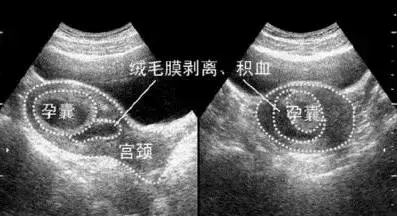

六、 绒毛膜下血肿

胚胎着床后会在表面形成绒毛膜,是构成胎盘的胎儿部分。当绒毛膜和子宫壁分离时会引起出血,出血量不固定,颜色偏暗,亦可无症状,仅在B超检查时发现孕囊周围的低回声出血区。如果无阴道流血或少量阴道流血不伴其他异常情况,多自然停止出血,不影响胎儿预后;如阴道出血量大、持续时间长、伴腹痛,B超提示出血面积增加可能导致宫内感染或不可避免的流产。

(图:B超下绒毛膜血肿)